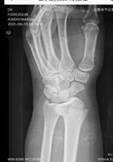

1)复杂断肢(指)再植修复:完成了9个月大婴儿断指再植手术,是当时世界上报道年龄最小的再植病例;完成世界第17例十指完全离断再植手术,并成为世界第一例功能完全恢复的病例。

2)四肢大范围组织缺损、大段骨缺损修复与功能重建:采用吻合血管神经的皮瓣移植修复、采用多个组织组合移植修复大面积皮肤缺损、骨缺损及其他组织缺损,采用骨段牵伸滑移技术,修复四肢长骨大段骨缺损及重建肢体功能。